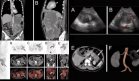

Los análisis de laboratorio no evidenciaron leucocitosis ni elevación de marcadores inflamatorios. Una tomografía computarizada (TC) abdominopélvica con contraste reveló líquido libre intraperitoneal sin presencia de neumoperitoneo, y se interpretó inicialmente como compatible con una posible torsión ovárica izquierda.

El equipo de ginecología procedió a una laparoscopia diagnóstica, en la cual se identificó un gran quiste ovárico sin torsión y una importante cantidad de líquido libre, sin evidencia de patología ginecológica que justificara los hallazgos. Ante esto, se solicitó la valoración del equipo de cirugía general, que realizó una segunda exploración laparoscópica, encontrando una perforación de 5 mm en la pared anterior del remanente gástrico.